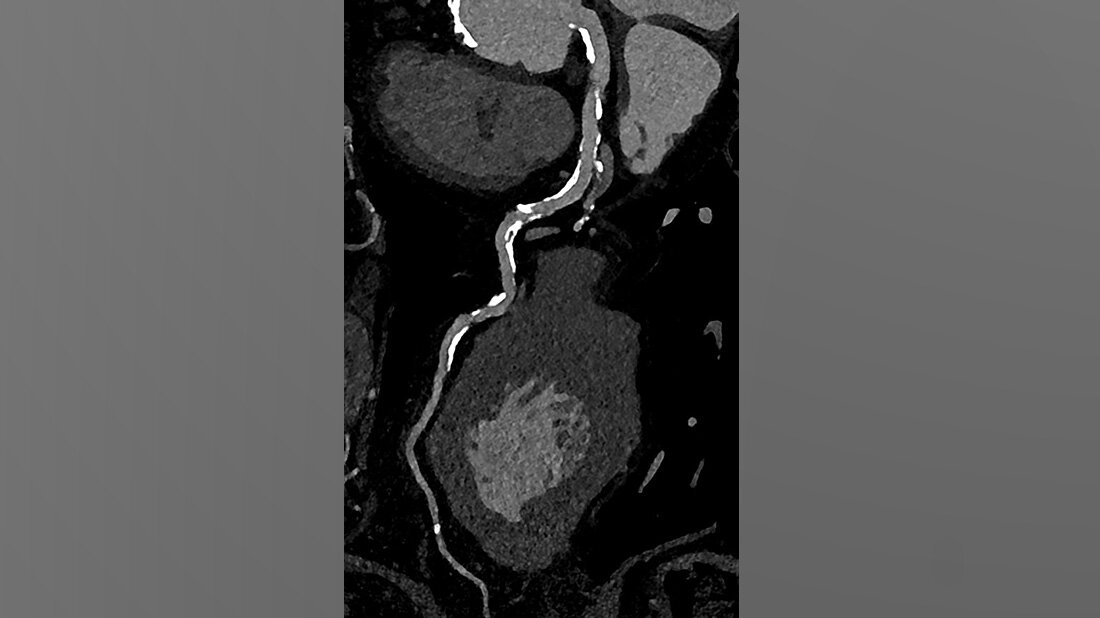

Die koronare CT-Angiographie eignet sich besonders gut zum Ausschluss einer koronaren Herzerkrankung bei Patientinnen und Patienten mit niedrigem oder mittlerem Risiko für Veränderungen der Herzkranzgefäße. Bei Personen mit hohem Risiko gestaltete sich dies bislang aufgrund von häufig auftretenden koronaren Verkalkungen und Stents jedoch schwierig.

Muhammad Taha Hagar, Erstautor der Studie und Arzt der Klinik für Diagnostische und Interventionelle Radiologie am Universitätsklinikum Freiburg erklärt: „In klassischen CT-Bildern erscheinen Verkalkungen der Herzkranzgefäße oft größer als sie tatsächlich sind. Dieser Effekt ist umso stärker, je größer die Verkalkung ist.“ Dadurch konnte es bislang zu einer Überbewertung von Verengungen und Plaques und in der Folge zu einer Überbehandlung kommen. Darum wurden diese Personen bislang schnell in den Herzkatheter überweisen oder in der Magnetresonanztomografie untersucht.

In der von Hagar und seinem Team durchgeführten Studie wurden 68 Probandinnen und Probanden mittels Photon-Counting-CT und einer invasiven Koronarangiografie als Referenzstandard untersucht. Die Patientinnen und Patienten litten alle unter einer schweren Aortenklappenstenose, einer gängigen, aber ernsthaften Herzerkrankung, die den Blutfluss vom Herzen zur Aorta reduziert oder blockiert. Die Photon-Counting-CT-Untersuchung zeigte sich sehr genau in der Erkennung oder dem Ausschluss der koronaren Herzerkrankung. Auch wurde die Bildqualität in fast 80 Prozent als gut oder hervorragend bewertet.